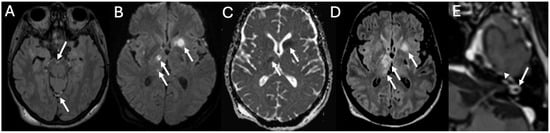

3.4. Labyrinthitis and Vestibulocochlear Neuritis

Imaging

3.5. Cochlear Hemorrhage

| Labyrinthitis/Vestibulocochlear Neuritis | Taxak & Ram 2020 [32]; Kharrat et al., 2024 [33]; Singh et al., 2023 [34]; Kim et al., 2024 [35] | Case reports and small series | Meningitis can cause secondary labyrinthitis with cochlear enhancement on MRI; progression to ossification possible if chronic. |

| Cochlear Hemorrhage (Rare Complication) | Perillo et al., 2024 [36]; Engelen-Lee et al., 2016 [37] | Case report; pathologic correlation study | First documented case of cochlear hemorrhage secondary to pneumococcal meningitis; likely due to microvascular injury. |